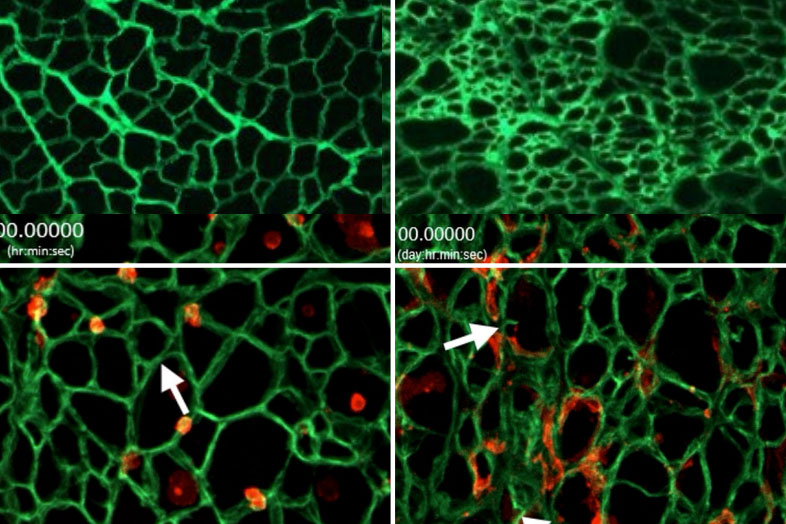

Giving children with immunodeficiency a chance to lead a normal life

For children with the rare condition ADA-SCID, day-to-day activities like going to school or playing with friends can lead to dangerous, life-threatening infections. If untreated, ADA-SCID can be fatal within the first two years of life. A blood stem cell gene therapy co-developed by UCLA’s Dr. Donald Kohn restored immune function in 59 of 62 children with ADA-SCID, with no serious complications reported.